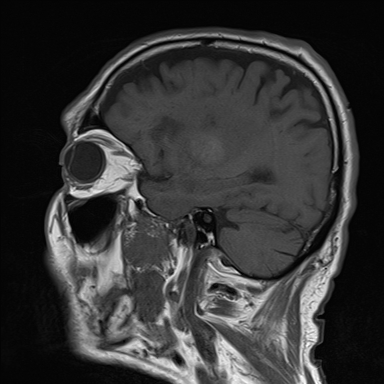

| SWI | T1 Sagittal |

![]() |

| T1-Weighted (T1WI) | Fat, subacute haemorrhage, gadolinium contrast | CSF, edema | Anatomy, post-contrast enhancement, haemorrhage staging |